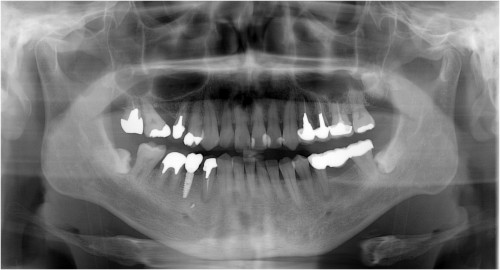

術 前